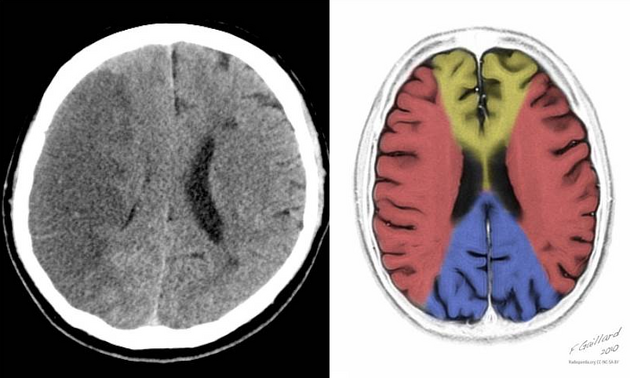

AVC isquêmico extenso da artéria cerebral média: quando a clínica antecede a tomografia

Estava eu na sala vermelha, assumindo o plantão, quando fui reavaliar um paciente que já se encontrava no leito havia algumas horas. A história trazida pela filha era de um quadro neurológico em evolução havia cerca de 18 a 24 horas. E aqui já começo com uma das primeiras lições práticas do plantão: o relógio […]